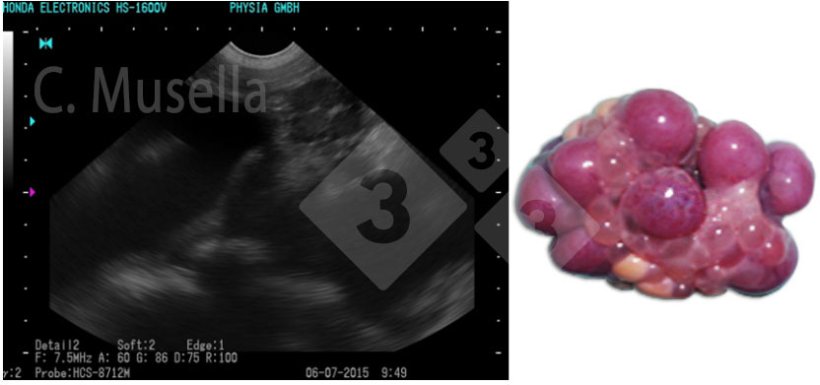

Figura 2. Folículos em ovulação